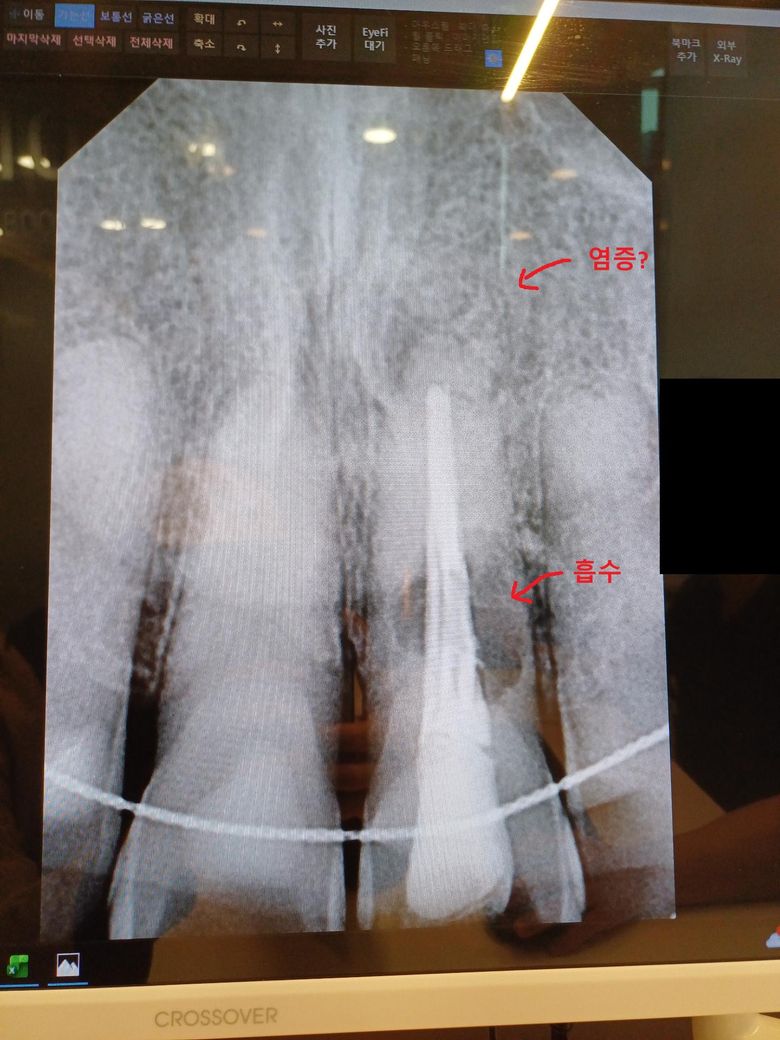

거의 10년 전 쯤 앞니에 충격으로 색상이 거무스름 하게 변하기 시작해서 신경 치료를 받았습니다. 염증으로 뼈가 녹았다고 하셔 이빨에 구멍 뚫고 잇몸? 도 절제해서 수술했던 기억이 있습니다. 잇몸 열고 수술 하는 게 지금 알아보니 치근단절제술 인 것 같고 재수술 성공 확률이 낮다고 들었습니다.

최근 그 부위가 붓고 통증이 있어 치과에 방문하니 임플란트를 권유 받았습니다. 사진 상 위쪽에 염증?과 아래쪽 부분에

흡수?가 있어서 임플란트를 해야 한다고 말씀하시더라고요...

치아의 내흡수가 발생한거 같습니다. 저정도 상태라면 치아를 발치하고 임플란트를 하시는게 좋을것같습니다.

사진상으로 봤을 때에는 치아에 내흡수가 일어나고 있는 것이며 발치를 해야할 것 같습니다.

치아뿌리 즉 치근 흡수가 일어나고 있습니다. 치근흡수가 된 치아는 더 이상 살릴 방법이 없습니다. 지금 통증이 있다면 뽑는 것 말고는 다른 선택이 없습니다. 뽑은 후에는 임플란트 해야 합니다.

내흡수가 진행되고 있기 때문에 치근단 절제술을 한다 하더라도 재신경치료도 한번 더 해야 하고 그러면 성공확률은 더 낮아집니다

한번 해볼 순 있지만 너무 큰 기대는 하시면 안됩니다